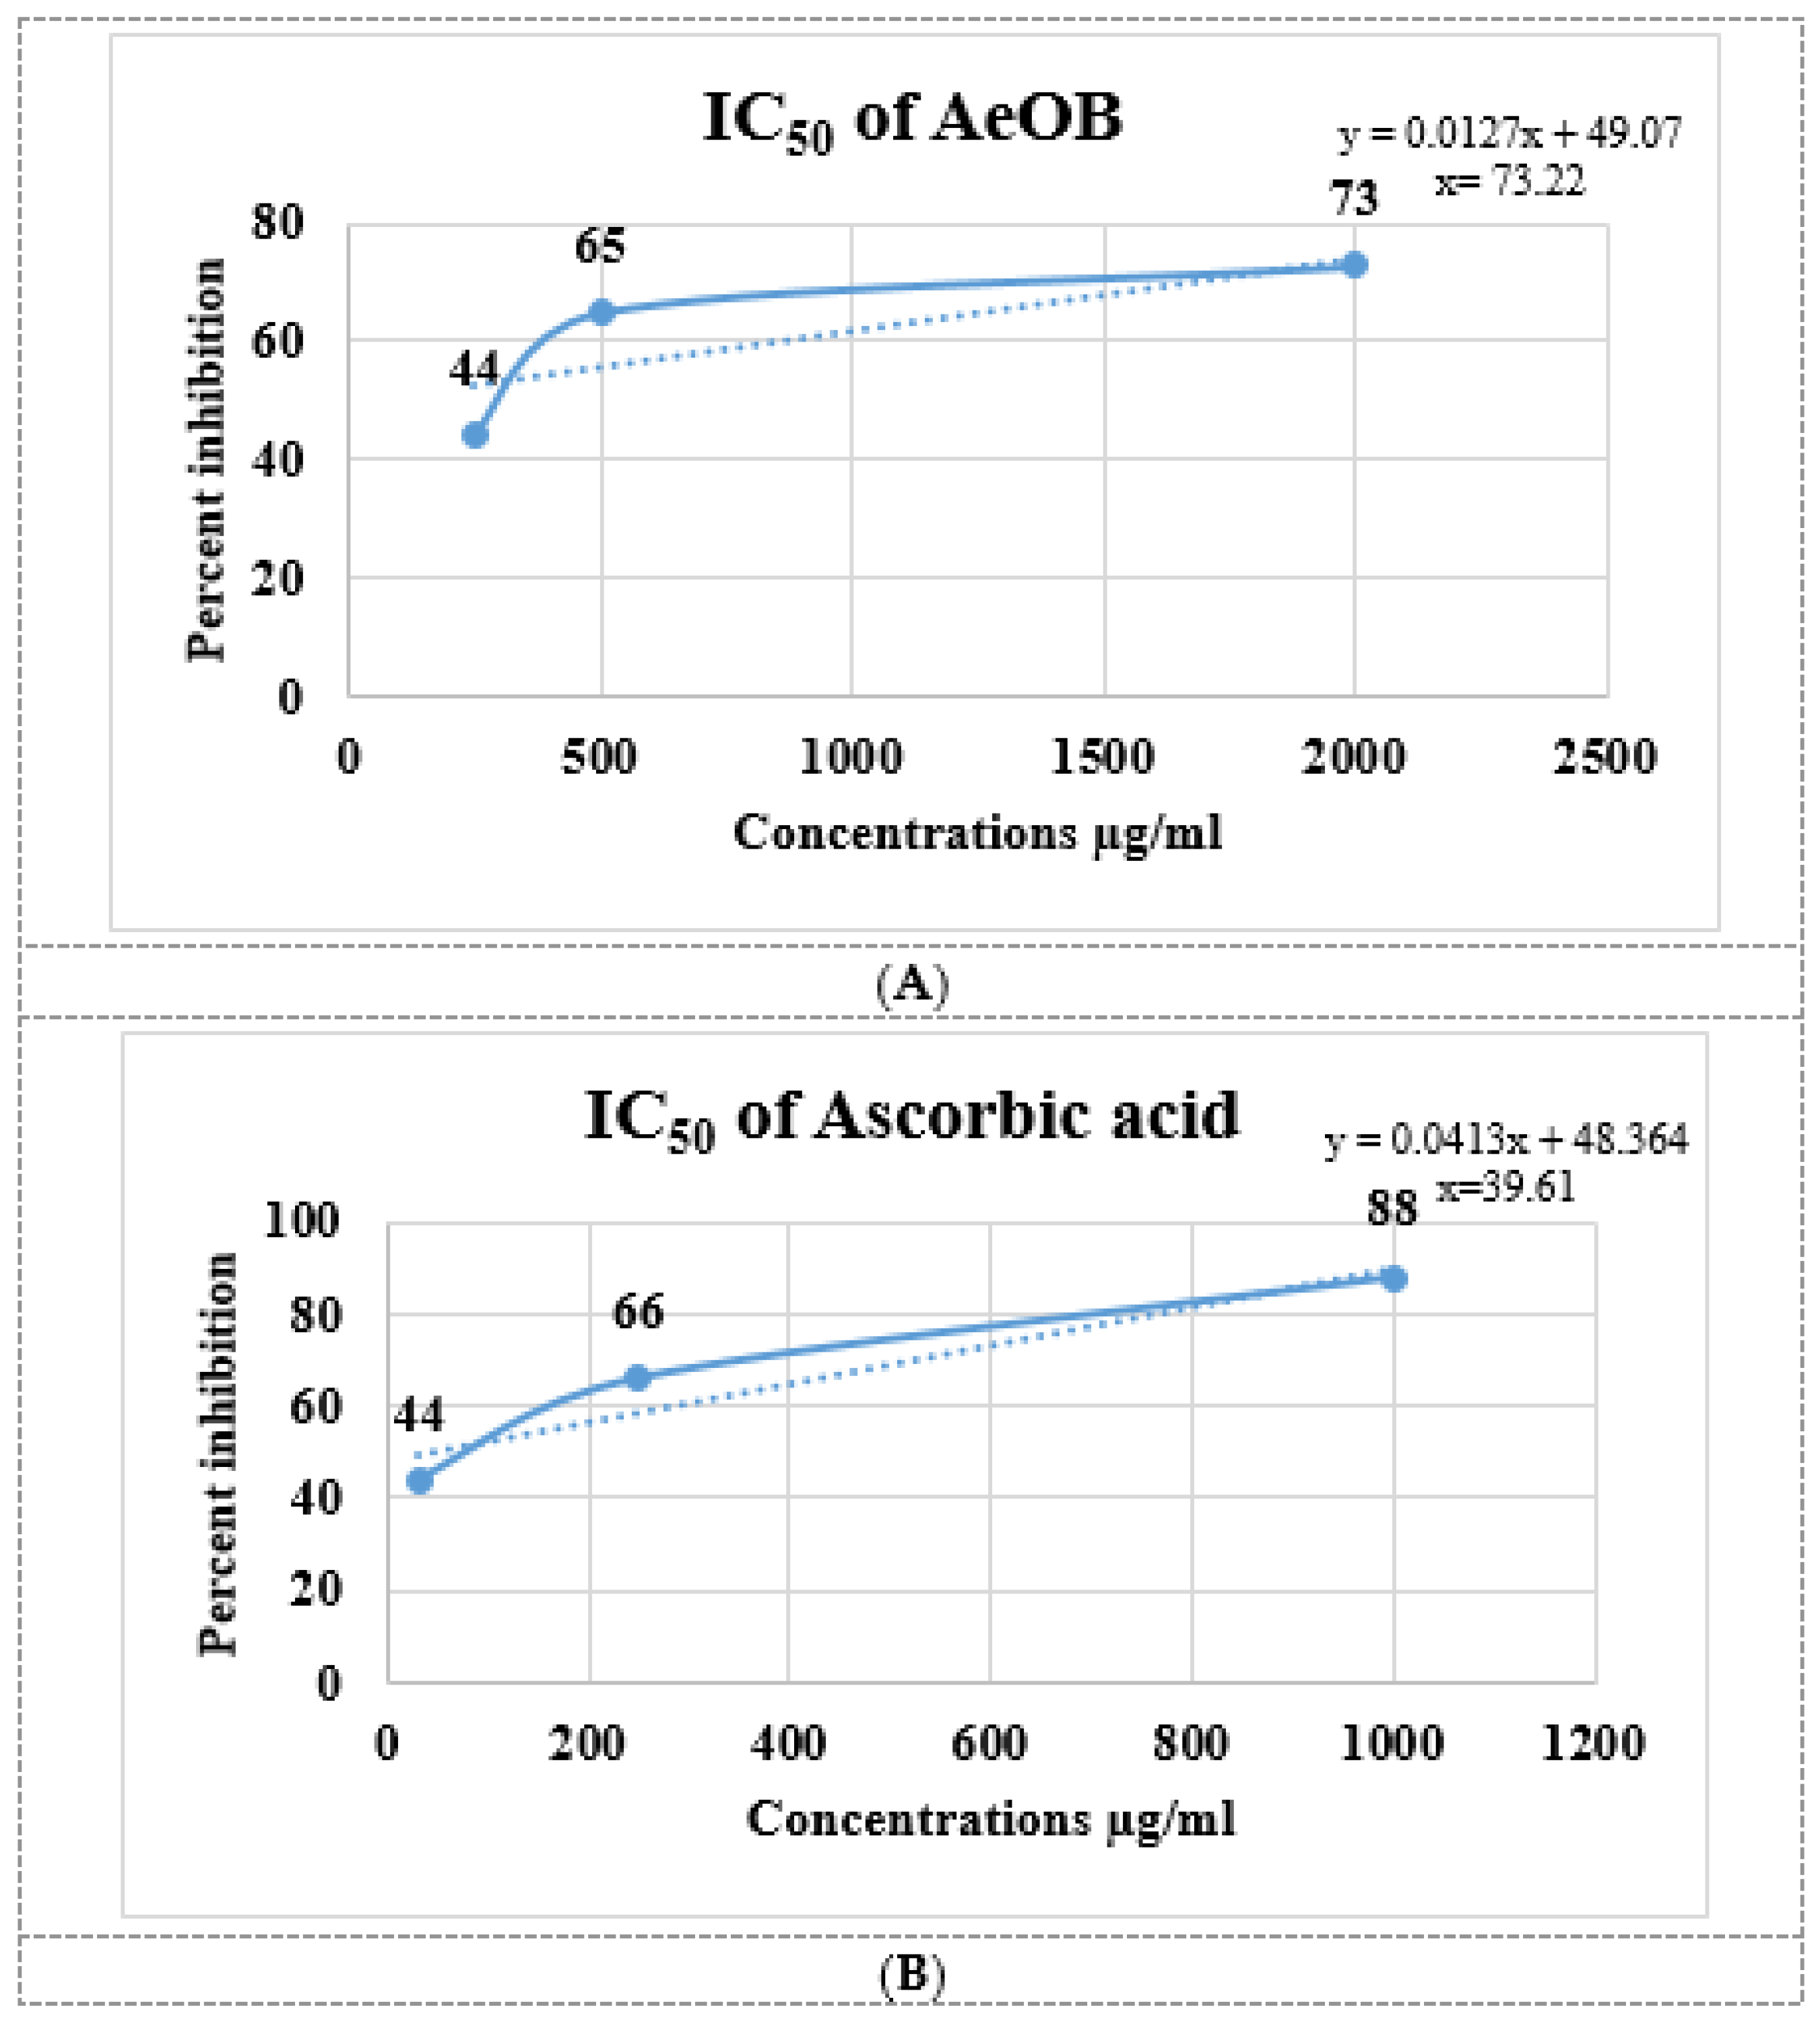

2.4. In Vitro Antioxidant Activity by 2,2-Diphenyl-1-Picrylhydrazyl Assay

4.6. In Vitro Antioxidant Activity by 2,2-Diphenyl-1-Picrylhydrazyl Assay